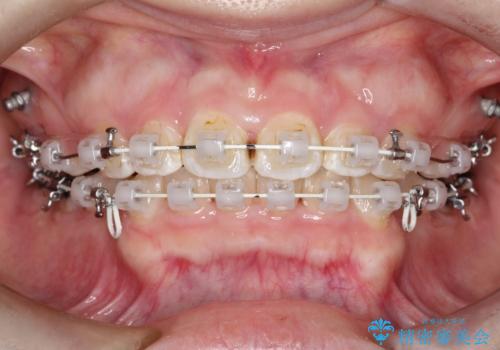

上下左右小臼歯を抜歯して審美装置で治療を行いました。

抜歯したスペースをきちんと下げることができるように、矯正用のアンカースクリューを用いて治療をしております。